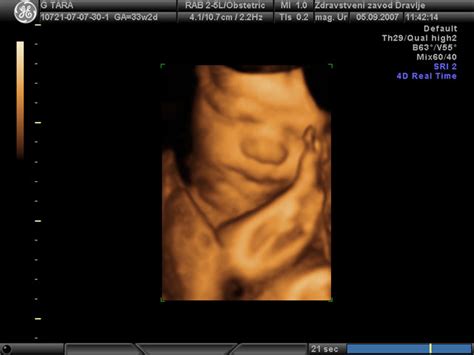

Plod se začne gibati že zelo zgodaj v nosečnosti, vendar teh nežnih gibov, kot so upogibanje in iztegovanje telesa ter nenadzorovani gibi okončin, sprva ne čutimo. Ti zgodnji premiki, ki jih lahko opazimo pri ultrazvočnem pregledu, so opazni že okrog osmega tedna nosečnosti. Ko plod raste in se razvija, postajajo gibi vse izrazitejši in močnejši.

Med 20. in 25. tednom nosečnosti postajajo gibi ploda vse bolj izraziti in močnejši. Ko otrok zraste in postane močnejši, v maternici pa ima še vedno dovolj prostora, se gibi spremenijo v izrazita brcanja, ki jih je mogoče opaziti tudi od zunaj.

Po opazovanju prvih, sprva šibkih gibov, ki so podobni zvijanju, nastopi obdobje, ko so plodovi gibi pogostejši in močnejši. Naslednjih deset tednov otrok postaja vse bolj aktiven, nosečnica pa čuti njegove brce, premikanje rokic in prevračanje. Od 24. do 28. tedna lahko nosečnica čuti tudi kolcanje ploda - blago, ritmično poskakovanje. V tem obdobju plod že lahko reagira na določene zvoke in znane glasove.